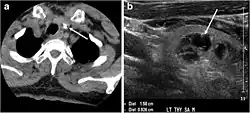

- Fig. 4. A 45-year-old male patient presented with anterior mediastinal metastatic PTC lesions and occult primary on imaging. Histopathology examination of the resected thyroid gland revealed micro-foci of PTC; the largest, in the isthmus, measured 4 mm. a transverse greyscale ultrasound of the thyroid demonstrates homogeneous gland with normal echogenicity and size. No focal lesion or micro-calcifications. b Non-enhanced CT scan obtained as part of PET/CT examination shows a heterogeneous, large, relatively dense anterior mediastinal mass (white arrow) with peripheral calcification (arrowheads). Thyroid gland has normal CT appearance with no abnormal FDG uptake (not shown).[1]

- Fig. 7. A 51-year-old female patient post total thyroidectomy for PTC with elevated thyroglobulin measurement. an Axial non-enhanced CT scan of the neck at the level of the thyroid bed demonstrates a well-defined, rounded, homogenously dense soft tissue situated between the trachea and left internal jugular vein (white arrow). b Transverse ultrasound image of the neck demonstrates a well-defined, homogeneous, hypoechoic soft tissue nodule measuring 6 mm (white arrow) with no detected micro-calcifications. Biopsy showed a predominantly residual normal thyroid tissue with micro-foci of PTC.[1]